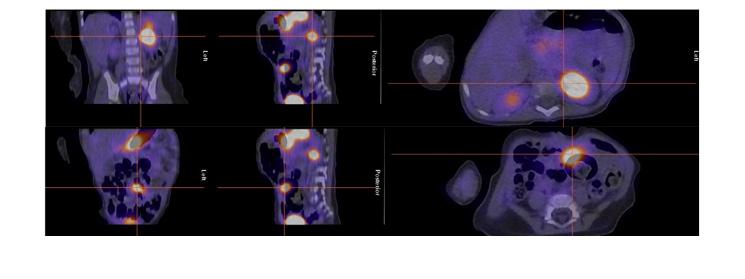

Figure 7 : Adolescente admise avec hémorragie basse massive. Préparation avec famotidine intraveineuse. Mise en évidence sur l’étude dynamique ( A ) puis sur le cliché statique ( B ) d’un foyer ombilical augmentant en intensité et en taille (flèche). La relation du diverticule contenant de la muqueuse gastrique avec l’ombilic est bien démontrée sur le SPECT-TDM (C). La pathologie de la chirurgie effectuée dans la foulée via laparotomie et non laparoscopie étant donné les trouvailles a démontré un Meckel de 6 x 2 cm contenant de la muqueuse gastrique, avec aspect perforé associé à un canal omphalomésentérique de 0,5 x 0,5 x 0,5 cm. Moins de 4 heures se sont écoulées entre l’arrivée de la patiente à l’urgence et la chirurgie.

Dans notre expérience, l’étude SPECT-TDM faible permet de confirmer les trouvailles planaires et de mieux le localiser par rapport aux structures normales pour la planification opératoire (figure 7 ). Dans notre expérience également, quoiqu’aucun diverticule de Meckel n’ait été identifié uniquement sur l’étude

Meckel n’ait été détecté uniquement sur SPECT, le SPECT/TDM a offert une meilleure localisation, une clarification des résultats douteux sur l’imagerie planaire et pour certains un diagnostic alternatif.

En résumé la scintigraphie au Pertechnétate de Tc99m continue à jouer un rôle important dans la détection de la muqueuse ectopique. Une préparation adéquate incluant l’utilisation de la famotidine IV et une mise en image complète incluant le SPECT-TDM permet d’optimiser la technique. Dans notre expérience, bien qu’aucun Meckel n’ait été détecté uniquement sur SPECT, le SPECT/TDM a offert une meilleure localisation, une clarification des résultats douteux sur l’imagerie planaire et pour certains un diagnostic alternatif.